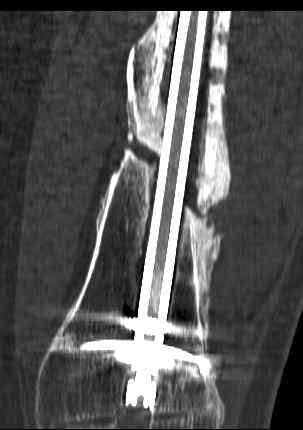

16 yr old boy, high energy motorcycle trauma trauma in July 2005 with:

- hip dislocation + acetabular fracture L

- distal femoral fracture L

- tibial shaft fracture L

- metatarsal fractures L

july 05: LISS femur, LCP plate tibia, double recon. plate post. acetabulum

oct 05: cancellous bone graft femur

aug 06: blade plate + bone graft

nov 06: revision blade plate

feb 07: retrograde nail + bone graft + BMP

may 07: dynamisation nail

sept 07: locking screw removal (max. dynamisation reached)

nov 07: persistant non-union distal femur; other fractures healed uneventfully.

All with gradual/partial weightbearing etc. Currently 50-100% weight bearing, no pain.

Soft tissues are intact. No smoking or diabetes.CRP <2